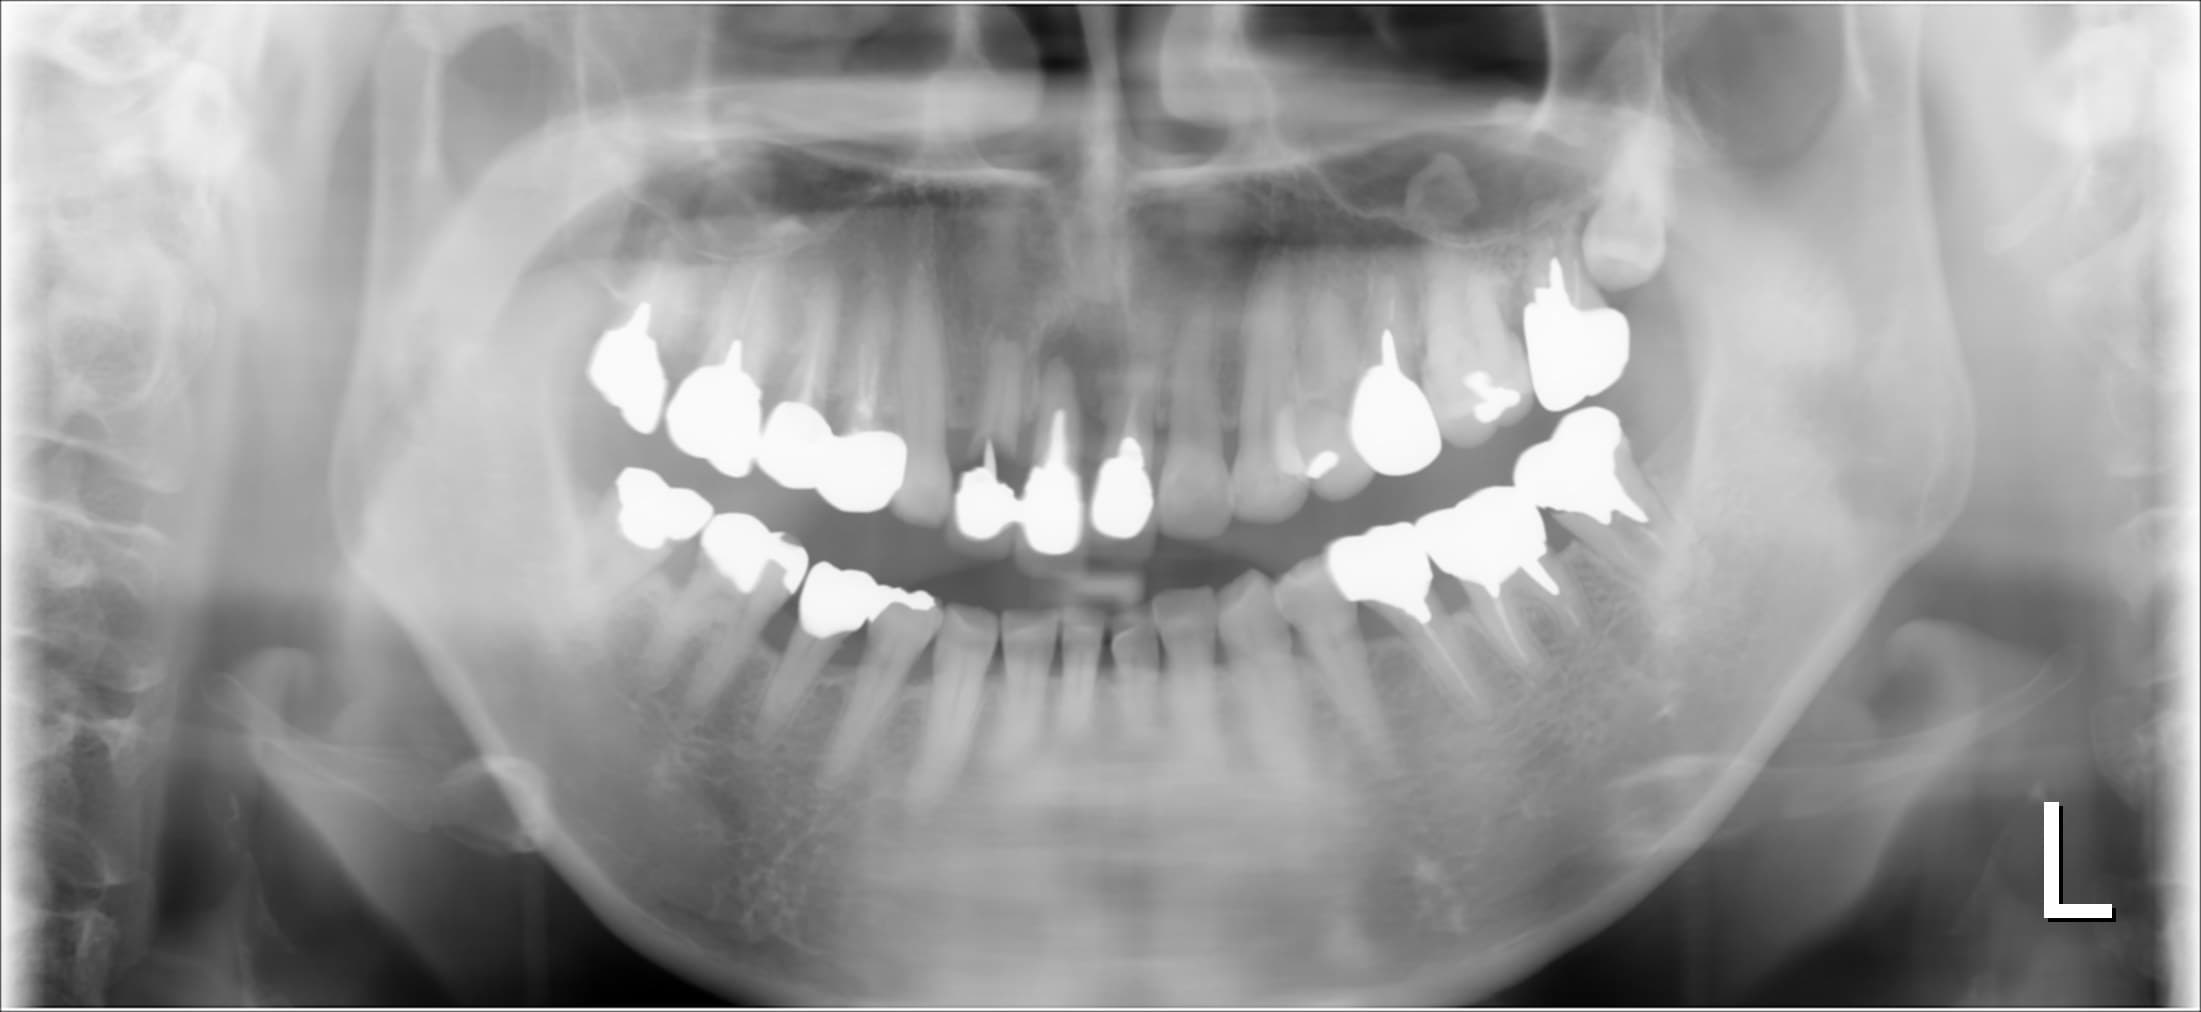

歯がぐらぐらして抜けそう・・・

こんにちは。 南館歯科クリニックの歯科衛生士の山崎です。 今回ご紹介する歯周治療のケースは、80代男性の方です。 重度の歯周病で、出血、排膿があり、前歯や奥歯がぐらぐらで浮…